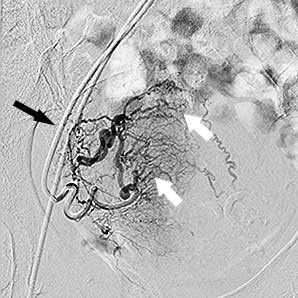

міома матки до емболізації    міома матки до емболізації

Права маткова артерія:

чорна стрілка - катетер, білі стрілки -

розширені артерії вузла